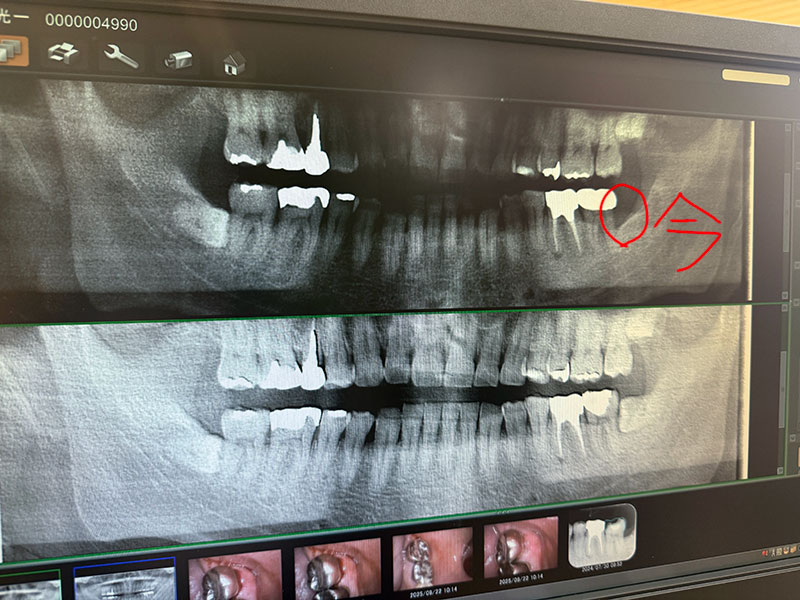

| 2025/09/22月 歯医者へ ↓前 次↑ 女王送り後、10時に歯医者へ。本当は昨日から大阪入りして今日サソリ練習のハズでしたが大阪のホテルの代わりに?こっちを予約しました。。1年ブリか、前回は半年に1回と決意したのにサボってたので案の定痛くなったか。。 ![]() おそらく歯周病とのこと。 ![]() 親知らずを抜いた影響で加齢もありこうなったらしいです。もう1本も同じリスクがあるとな。まあ半年に一回来るのを守れば大丈夫か。ちなみに女王は虫歯が10本ぐらいあってかつワイと同じ場所に親知らずも都合4本あって若いうちに全部抜いた方が良いとのことで受験後に敢行という流れに。 ![]() ジョガーからもらった名レトルトを食らいました。ドコとなく高校時代の学食を思い出しました、いつか現地で食べたい。 ![]() ミニボード用のカールコードのジャックを交換します。老眼でこういうの更にキビしくなってます、元々ヘタクソなのにw ![]() スタジオ練習無いのイタいけどモロ実験モードでVOXのアコAMP持って行こうと思います。 ![]() 明日の音まかす、リハ超重要やな。 ↓前 次↑ | ||||||